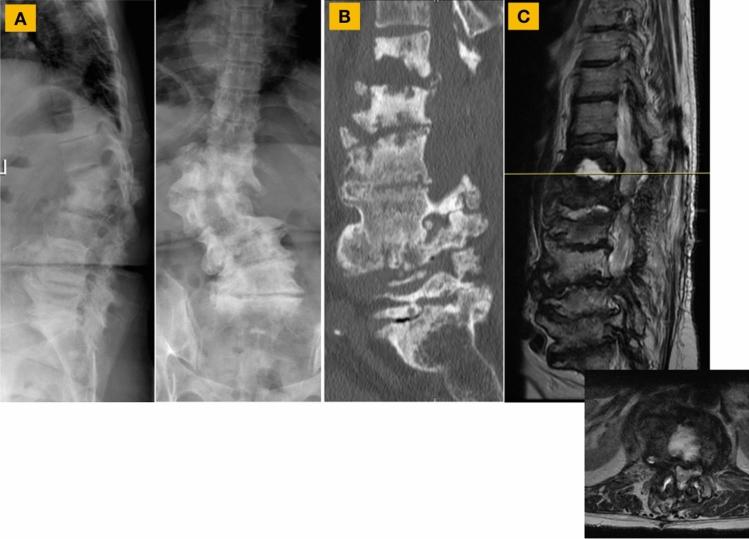

A 67-year-old female with a history of degenerative flatback and scoliosis and pathological fractures of T12 and L1 secondary to osteodisciitis underwent a single0stage L5-S1 ALIF and T9-pelvis posterior instrumented fusion with bilateral dual iliac screw fixation, revision T11-S1 decompression, and T12 and L1 irrigation and debridement and partial corpectomies. During the operation, non-pulsatile bleeding was encountered after creating an initial trajectory for the more proximal of the two left iliac screws. While the initial post-operative course was benign, the patient was readmitted for hypotension and anemia. Computed tomography of the abdomen/pelvis demonstrated a pseudoaneurysm (2.3 cm × 2.1 cm × 2.3 cm) of a branch of the left SGA. Diagnostic angiogram confirmed a pseudoaneurysm off of one of the branches of the left SGA. Endovascular embolization using multiple coils resulted in a complete cessation of blood flow in the pseudoaneurysm. At 2 years follow-up, no symptoms suggestive of recurrence of the pseudoaneurysm were reported.

一名67岁女性,有退行性平背和脊柱侧弯病史,因骨椎间盘炎继发T12和L1病理性骨折,接受了一期L5-S1前路腰椎椎间融合术(ALIF)和T9-骨盆后路器械辅助融合术,双侧双髂骨螺钉固定,T11-S1翻修减压术,以及T12和L1冲洗清创术和部分椎体切除术。手术过程中,在为左侧两枚髂骨螺钉中较近端的一枚创建初始通道后,出现了非搏动性出血。虽然术后初期病程平稳,但患者因低血压和贫血再次入院。腹部/骨盆计算机断层扫描显示左SGA分支有一个假性动脉瘤(2.3 cm×2.1 cm×2.3 cm)。诊断性血管造影证实左SGA的一个分支有假性动脉瘤。使用多个线圈进行血管内栓塞导致假性动脉瘤内血流完全停止。在2年的随访中,未报告提示假性动脉瘤复发的症状。